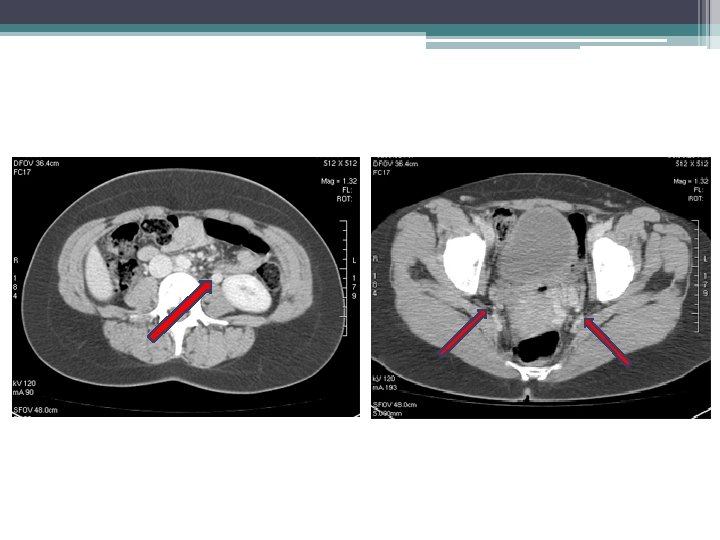

ACİL BAŞVURU (1. ay) • ŞİKAYET: Sol bacakta şişlik, ciddi ağrı, hareket kısıtlaması • RDUS: Sol eksternal iliak, ana femoral ven proksimalinde nonkanalize akut tromboz

VENOGRAFİ